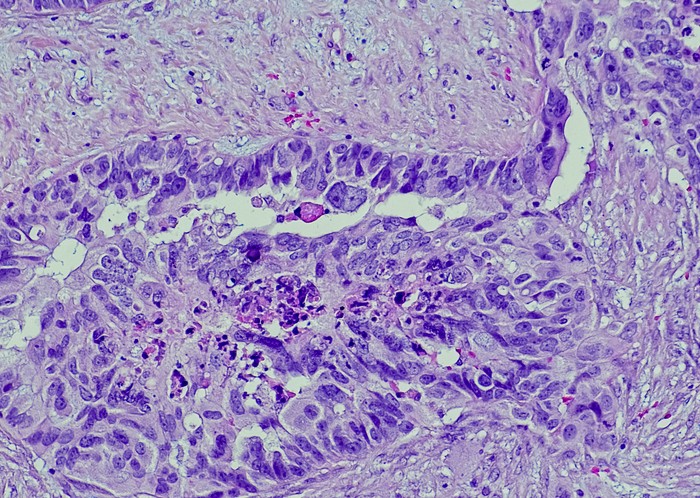

Featured photo at top of ovarian cancer cells. Photo/OGPhoto/iStock.